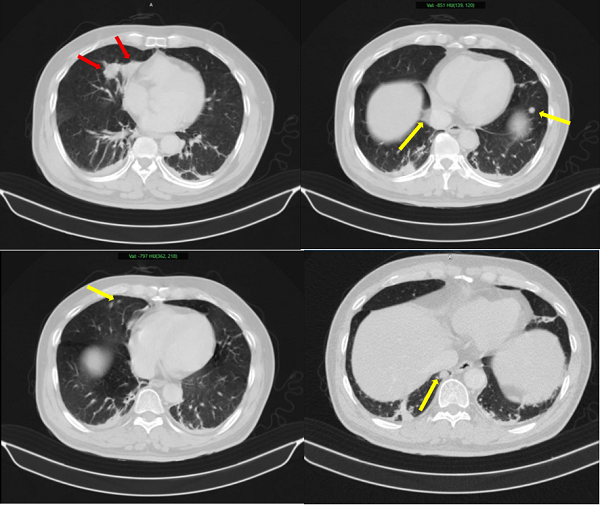

Hình ảnh 02 khối u bờ đa cung ở nhu mô thùy giữa phổi phải, dính vào màng phổi trung thất (mũi tên đỏ) kèm nhiều nốt đặc nhỏ rải rác nhu mô phổi hai bên (mũi tên vàng) gợi ý tổn thương thứ phát - Ảnh: BVCC